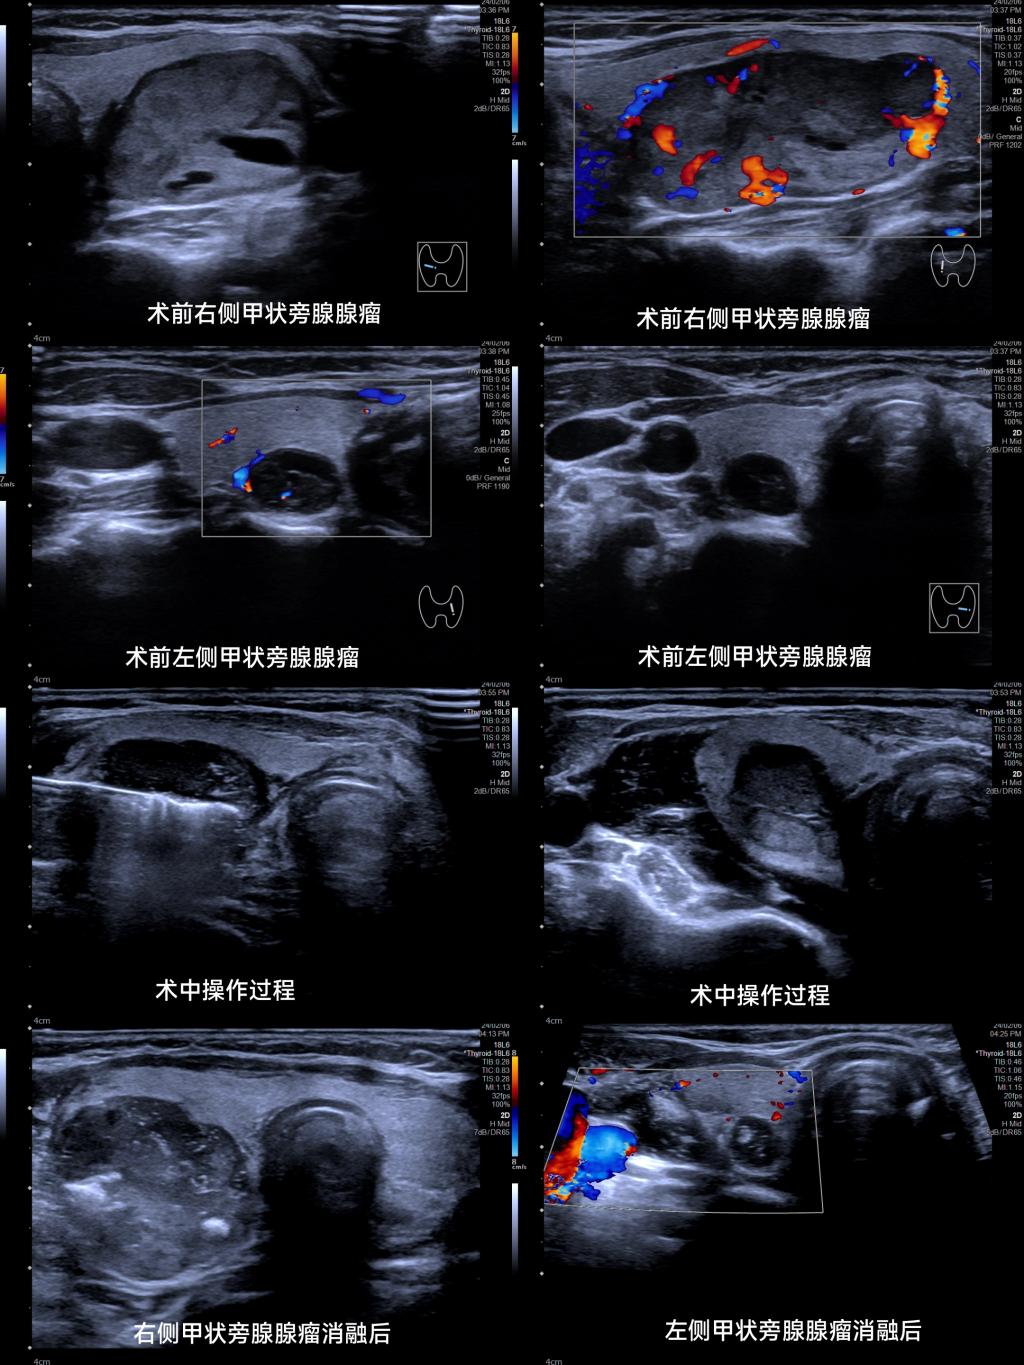

甲状旁腺腺瘤射频消融是一种治疗甲状旁腺腺瘤的介入性治疗方法,该技术是通过超声引导下,利用射频电极精确穿刺腺瘤,释放高频电能,使腺瘤组织局部坏死,达到治疗的效果。术中需要精确定位和控制能量的强度和分布,以确保足够的热量用于破坏腺瘤组织,同时避免对周围正常组织造成过多的热损伤。手术医生需要具备熟练的技能和经验,以确保射频能量的合理应用。

医用超声研究室主任周琦教授、姜珏主任医师及何鑫主治医师在术前对患者的甲状旁腺病变及胎儿进行详细的超声评估,并制定了个体化的射频消融方案及应急预案。2024年2月6日下午,医用超声研究室介入团队顺利完成该患者双侧甲状旁腺腺瘤射频消融治疗。手术过程中,超声科团队紧密协作,精准操作,顺利进行,手术时间仅15分钟,术后给予保胎治疗,患者无明显宫缩,胎动好,监测胎儿无异常。患者在术后2小时血钙值逐渐下降,术后1日甲状旁腺素(全段)降至57.920pg/ml正常范围,术后2周复查血钙已恢复正常2.24mmol/L。